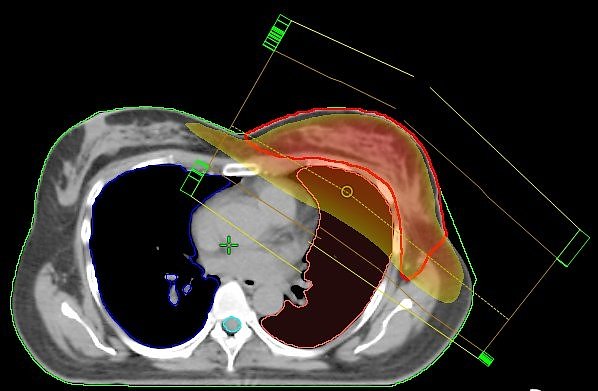

Normal: Stehfeldtechnik mit 2 Feldern (Standardtechnik); der Hochdosisbereich erfasst nicht nur das Zielvolumen (rote Kontur), sondern auch die umgebenden Risikoorgane (Lunge und Herzkranzgefäße), was zu Nebenwirkungen führen kann